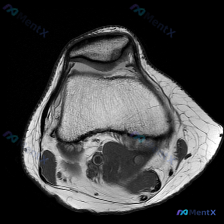

这张影像为髌股关节层面的轴位T1加权像,读片结果如下:

- 骨骼结构:髌骨、股骨内外侧髁形态完整,皮质骨连续,松质骨骨髓信号为正常脂肪高信号,没有骨挫伤、骨质破坏、骨赘增生等异常改变

- 关节软骨:髌骨后方软骨、股骨滑车软骨轮廓连续,没有明确的局灶性变薄、缺损,也没有看到软骨下骨的异常信号

- 关节与软组织:仅有少量正常滑液,没有过度积液,周围支持带、肌肉走行自然,没有肿块或异常信号

读片总结:单从这张T1轴位影像来看,没有发现明确的病理性改变。